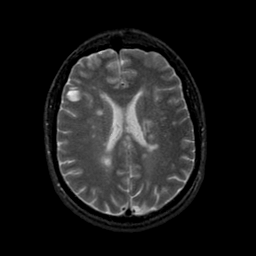

MR Study #9, April 14, 1991 -- Slice #31